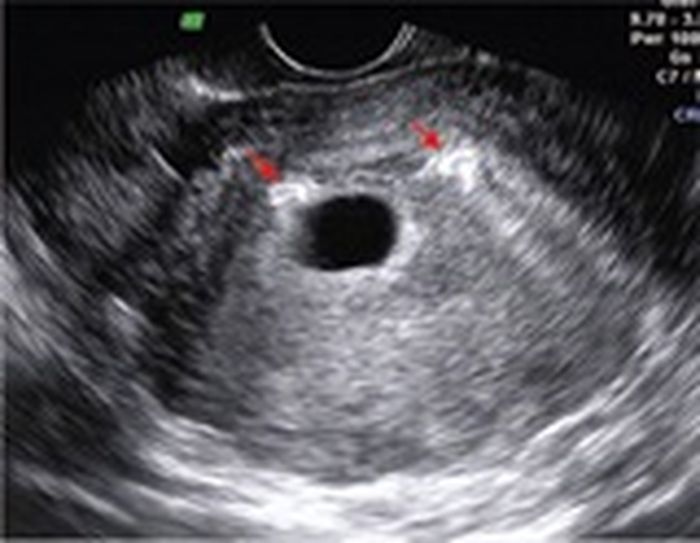

Dikutip dari livescience.com ternyata setelah ditelusuri dan hasil pemeriksaan tim medis, hasil mengejutkan didapat dokter karena IUD pertama yang dulu ia pasang pada uterus pasiennya itu hilang dan sudah berpindah ke kandung kemihnya.